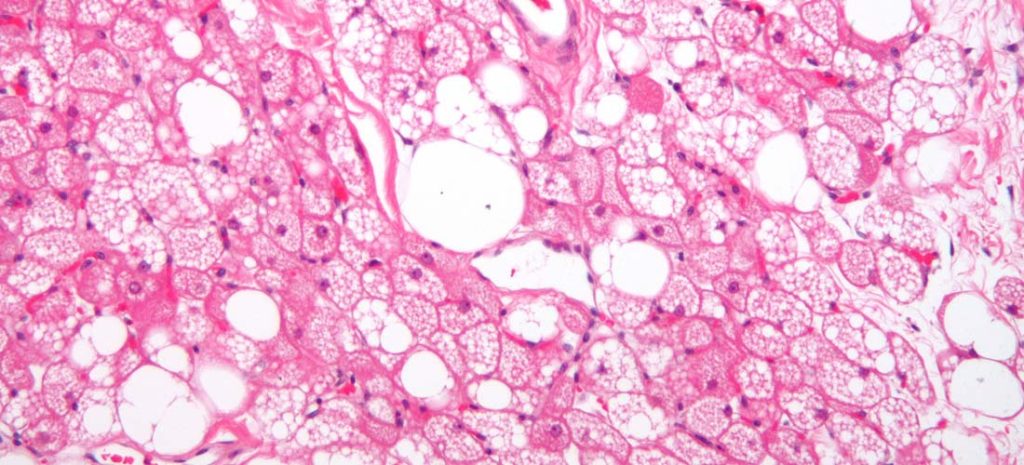

Long-term metabolic, adipose tissue improvements present after RYGB

Despite weight regain after bariatric surgery, long-term insulin sensitivity and adipose phenotypes remain improved in women with obesity, study findings show. Source: Healio | Read More